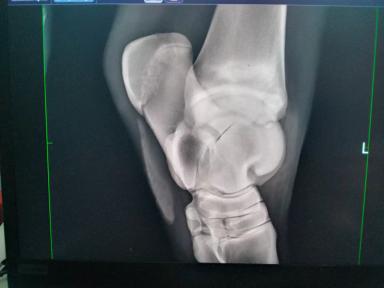

Здравствуйте. Кто может помочь в определении диагноза и лечении (видео ниже)?

Смотрели два ветеринара, но ничего не нашли. Лечение было проведено следующее: нитокс, айнил, катозал, ванночки с креалином, чередование мазей ихтиол и Вишневского. Корова уже месяц не наступает. Я бью тревогу, нашему ветеринару все равно: "ждите, когда выйдет инородное тело".